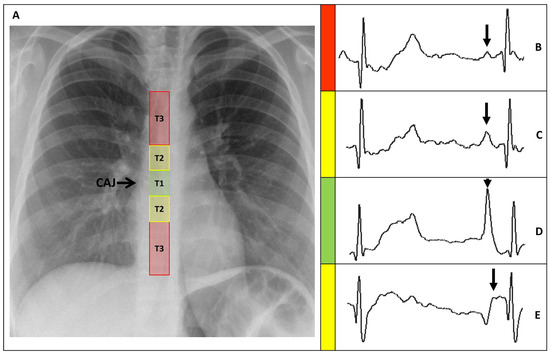

PICCs positions were classified, based on the distance between the catheter tip and the CAJ (DCAJ), as previously described and imaged [14]. The classifications were: T1: a final tip position of ±1 cm from the CAJ (optimal); T2: a tip position 1–3 cm above or below the CAJ (suboptimal); and T3: a tip position >3 cm below the CAJ or not in the SVC (inadequate, required repositioning) (Figure 3).

Figure 3. (A) Chest X-ray showing the CAJ localization. The tip of the catheter in T1 (within 1 cm of the CAJ) is considered optimal (green zone). The tip in T2 (within 1–3 cm of the CAJ) is considered suboptimal (yellow zone). The tip in T3 (more than 3 cm below the CAJ or not in the SVC) is considered inadequate and needs to be repositioned (red zone). (B) Intracavitary electrocardiogram. A catheter tip in T3, distant from the SVC, will feature a trace similar to the superficial ECG trace, with a P-wave lower than the Twave immediately preceding it. (C) Intracavitary electrocardiogram. A catheter tip in T2, nearing the CAJ, will feature a trace with increasing P-wave, equaling the Twave immediately preceding it. (D) Intracavitary electrocardiogram. A catheter tip in T1, positioned at the CAJ level, will feature a P-wave with maximal amplitude without initial negative deflection. (E) Intracavitary electrocardiogram. A catheter tip in T2-T3, beyond the CAJ, will present a decreasing P-wave and negative deflection. CAJ, cavoatrial junction (open arrow); SVC, superior vena cava; P-wave (closed arrow).